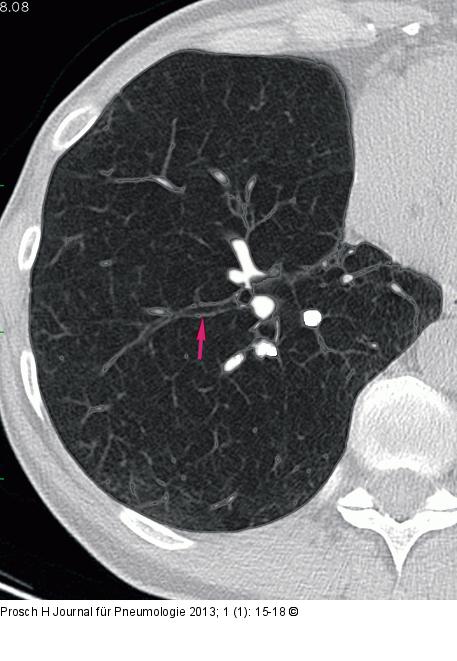

Abbildung 3: Computertomographie-COPD Ektatisch erweiterte Bronchien des Unterlappens als Ausdruck einer Bronchopathie bei einer Patientin mit COPD |

Abbildung 3: Computertomographie-COPD

Ektatisch erweiterte Bronchien des Unterlappens als Ausdruck einer Bronchopathie bei einer Patientin mit COPD |